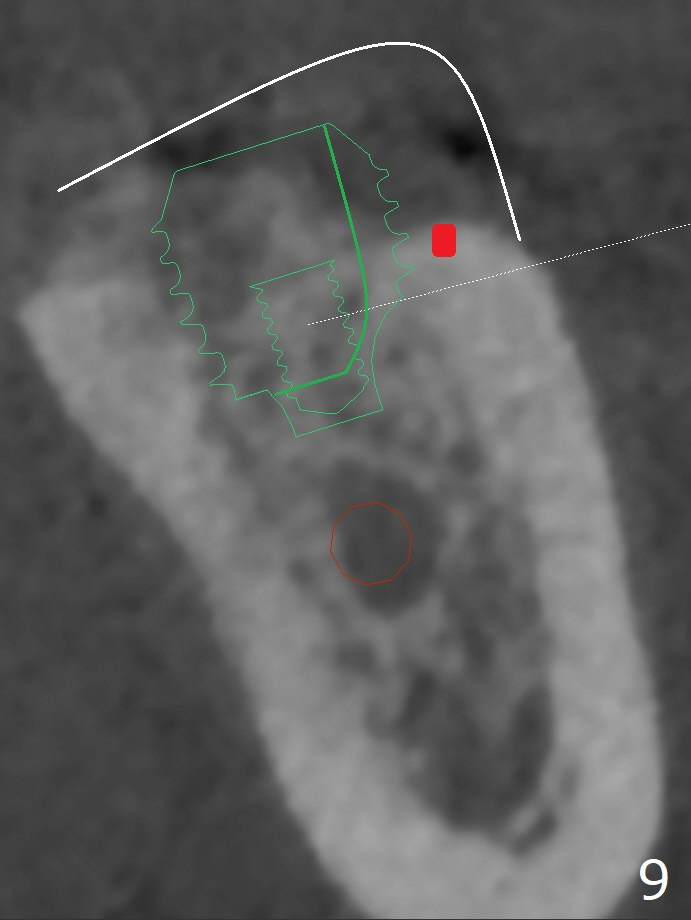

It appears that short implants could be placed mesial to the original sites (Fig.5,6), 5x6 and 5x5 mm at #19 and 18, respectively, with guide as lingual as possible. The exposed buccal threads will be covered by 3-D Bond (Fig.9 white line, post decortication (red)), collagen plug and PGA suture. Healing screws are most likely used, although healing abutments should be prepared if they help wound closure.